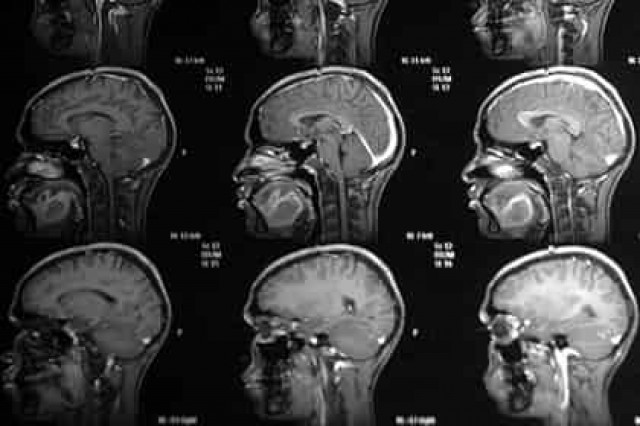

Ученые создали липосомы — наночастицы, состоящие из липидного бислоя, внутри которых находится жидкая фаза. Лекарства при этом могут находиться как в жидкой фазе, так и внутри бислоя. Отличительной особенностью частиц являются присоединенные к их поверхности лиганды — молекулы, облегчающие проход через ГЭБ. Ими могут быть трансферрины, интерлейкины, фолиевая кислота и лактоферрины.В ходе испытаний наночастиц были использованы здоровые мыши, а также мыши, которым вводилась линия раковых клеток U87MG (человеческая глиома) или GL261 (мышиная глиома). Опухолям было позволено расти в течение двух недель после имплантации, после чего в кровь грызунов были введены наночастицы.

В предварительном эксперименте грызунам без глиомы вводились наночастицы либо с трансферриновыми лигандами (Tf-NP), либо с фолиевой кислотой (Fol-NP), после чего их количество в тканях мозга определялось с помощью мультифотонной микроскопии через отверстие в черепе животных. Оказалось, что Tf-NP накапливались лучше, чем Fol-NP и наночастицы без лигандов. Tf-NP также успешно преодолевали барьер у больных мышей и накапливались в клетках на поверхности глиомы.